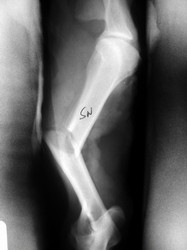

PRÁCTICAS CURSO DE FIJACIÓN EXTERNA PERFECCIONAMIENTO.

Húmero.